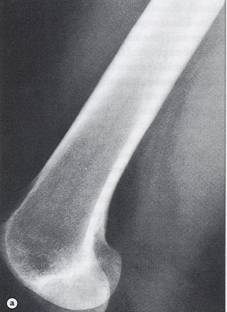

- radiografii osoase: osteoliza,

osteoscleroza sau lez mixte, reactie periostala, distructie corticala

Tumora cu celule gigante